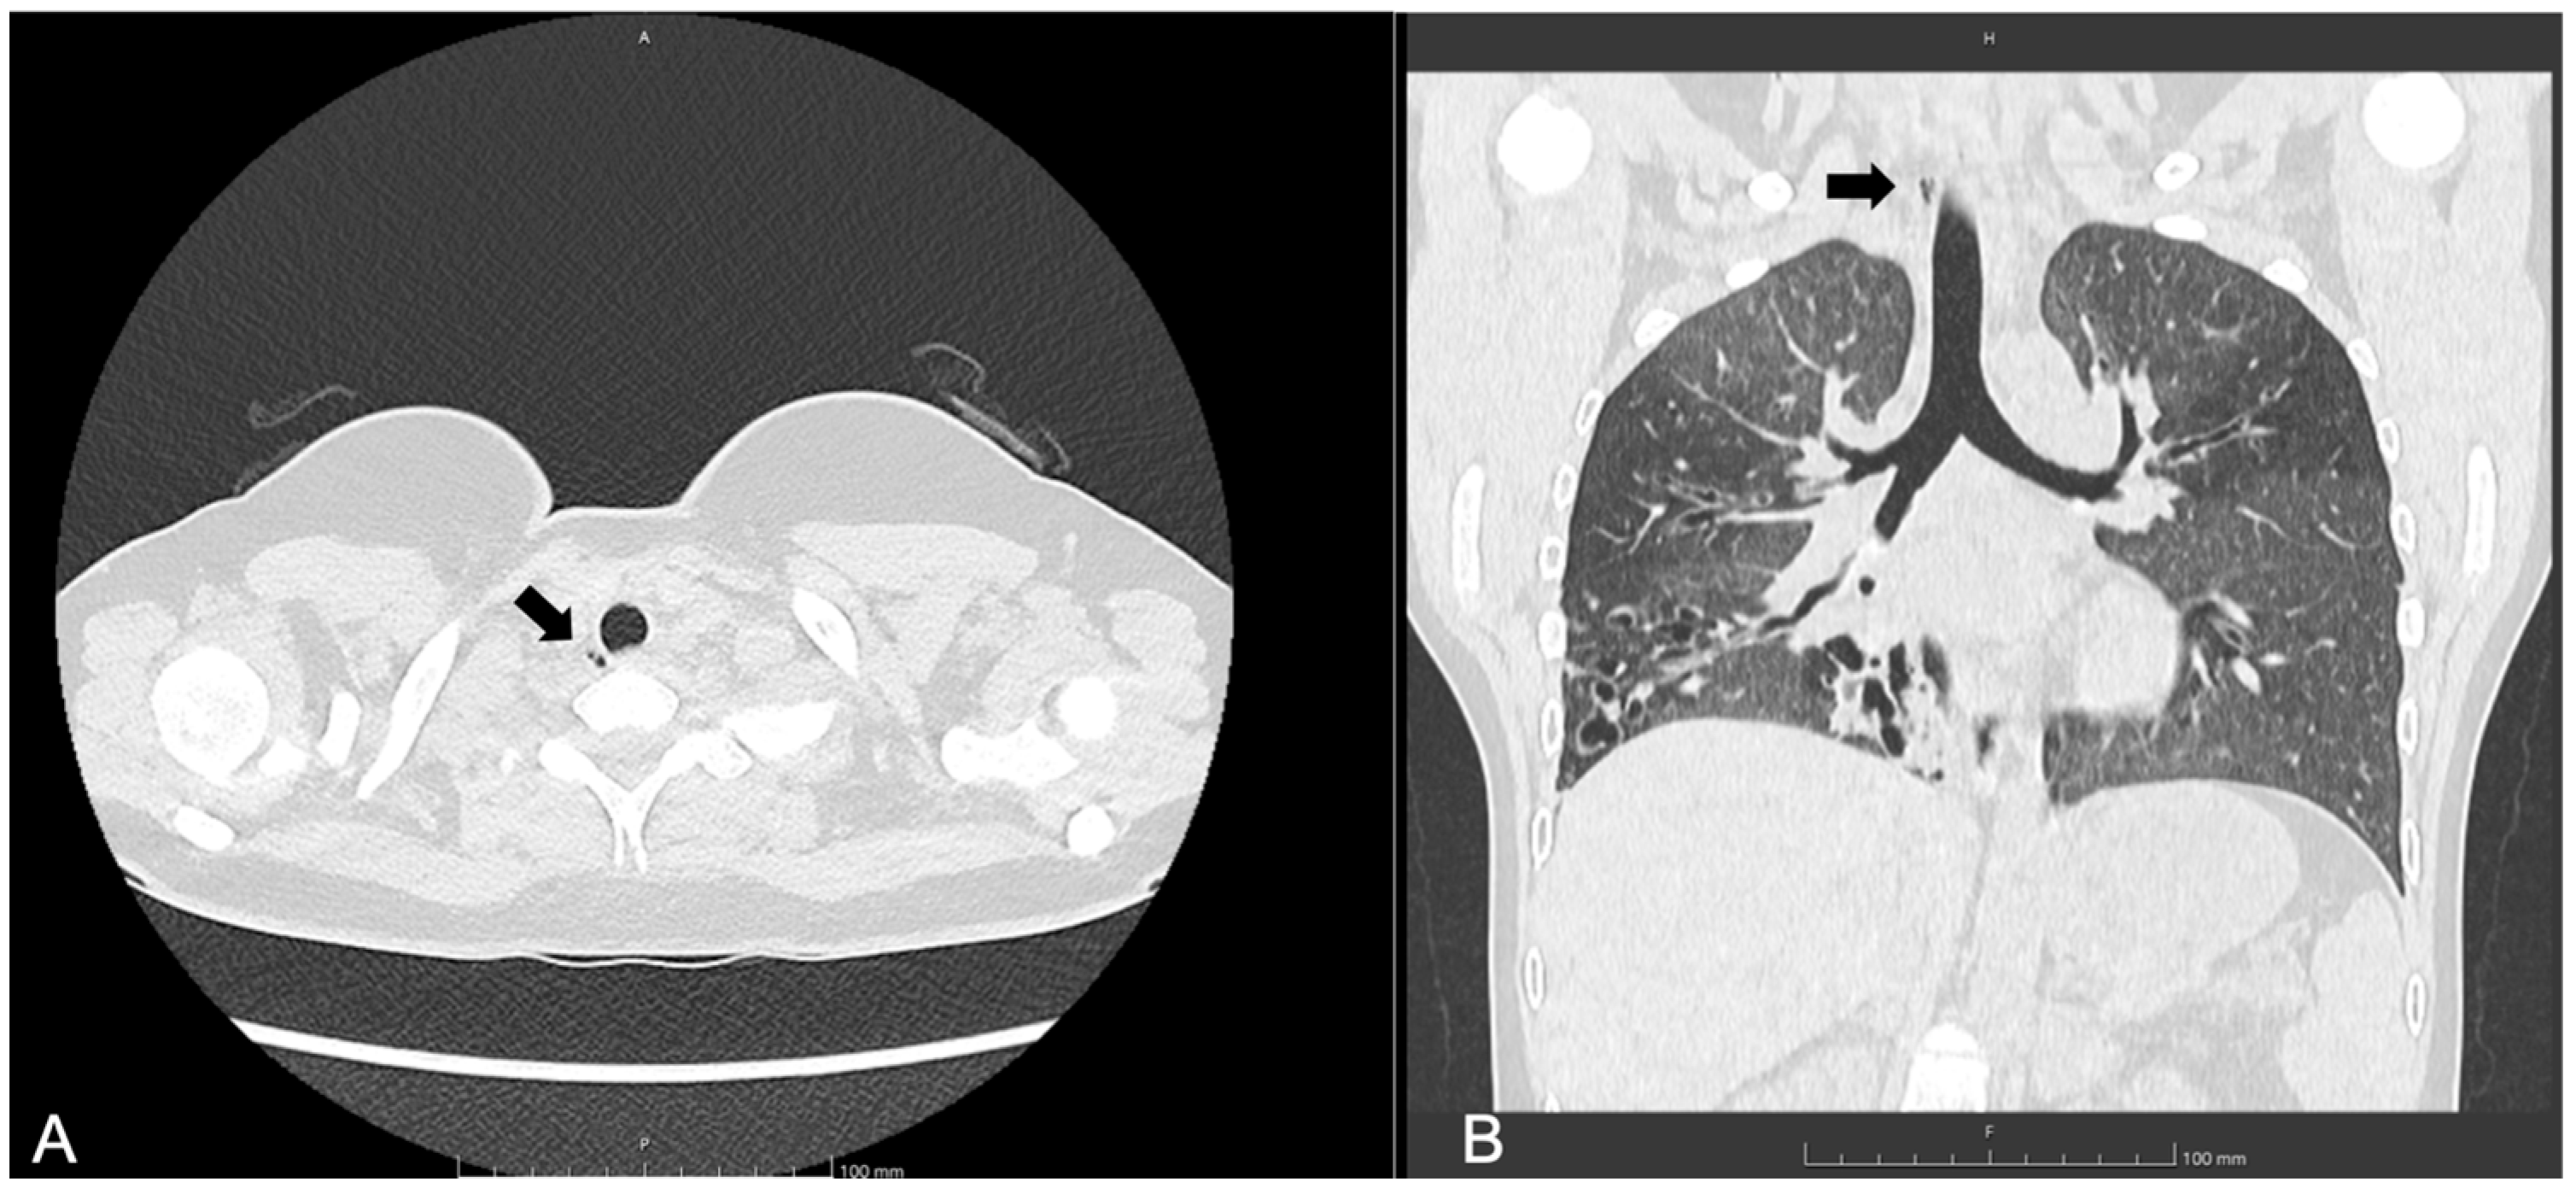

3.3. Patient 3

| 10, F | F508del/ F508del | SA, first PA detection | 117 | 16 | 1, 9, right posterolateral at T1 level | No | Visible radiologically, not endoscopically | Not yet performed |